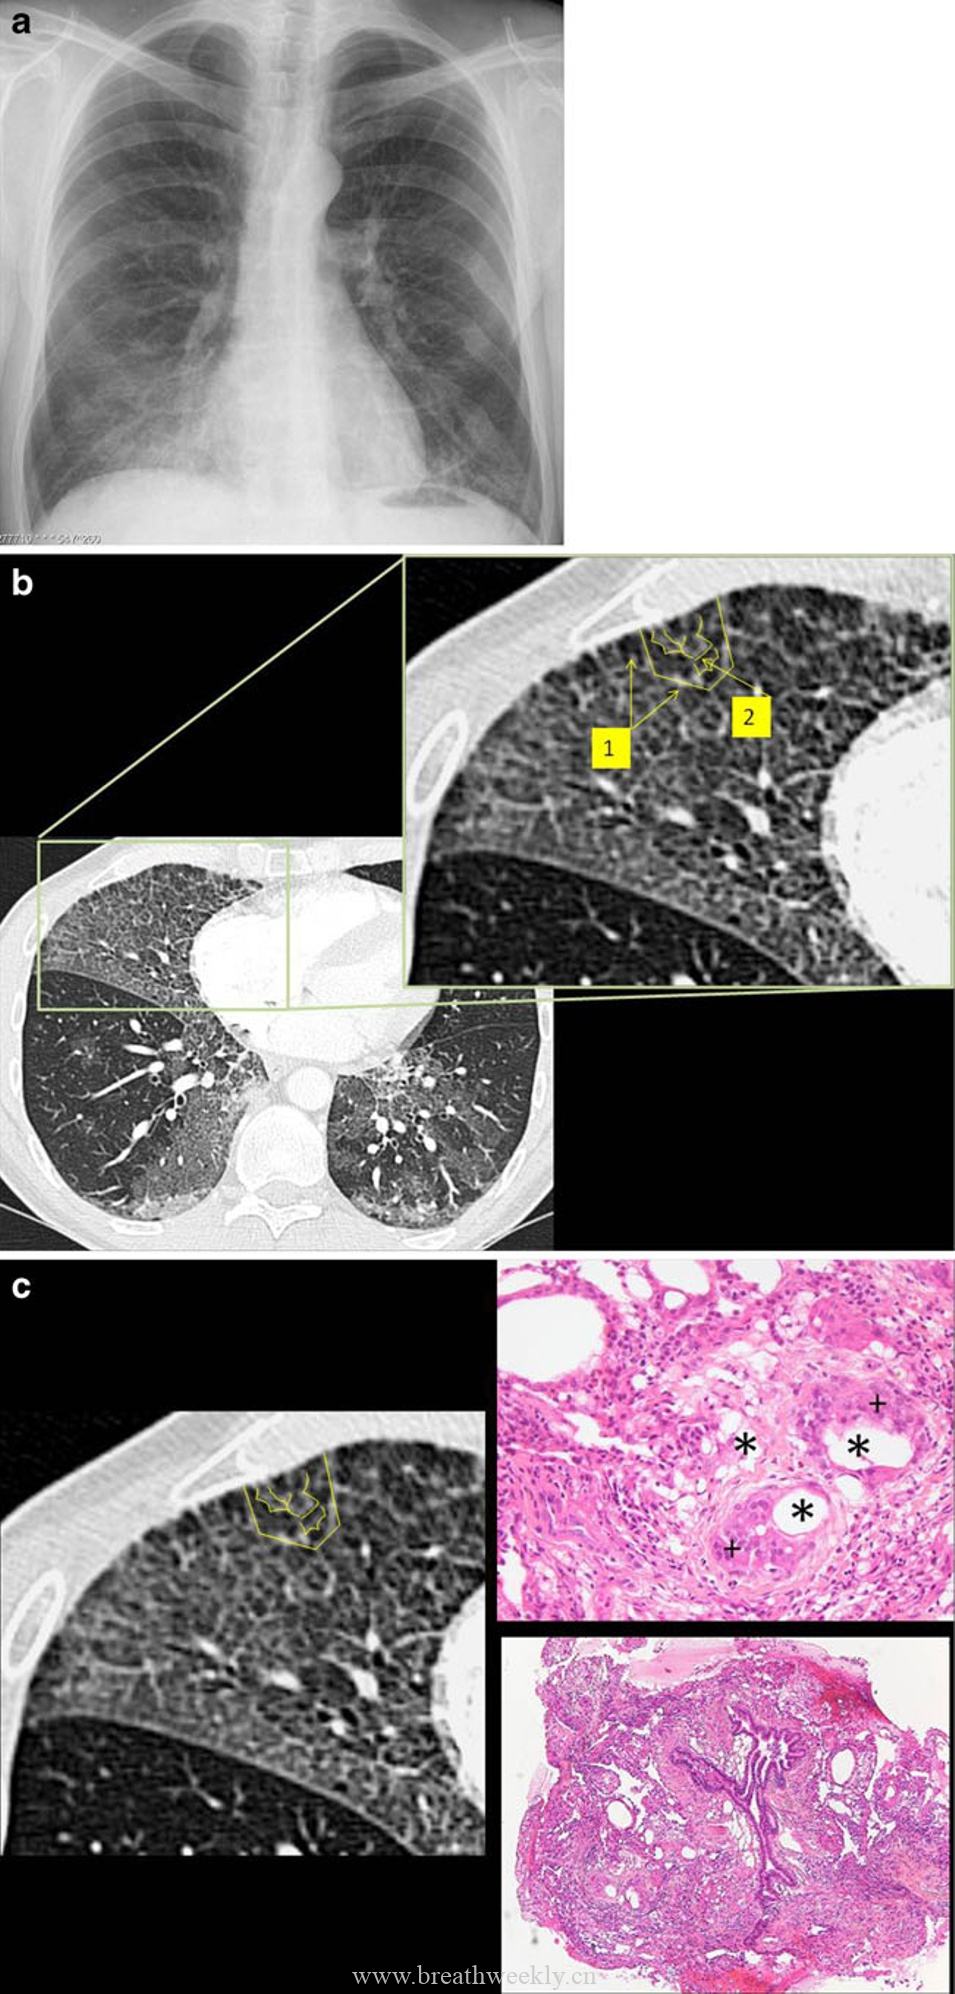

病例2:过敏性肺炎

临床资料:62岁女性,进行性活动后气短。

影像表现:CT显示地图样分布的铺路石征,以上肺为主。

病理对照:间质性肺炎,淋巴细胞、浆细胞浸润,可见上皮样肉芽肿,无纤维化。

在过敏性肺炎中,抗原-抗体复合物引起中性粒细胞炎症反应。亚急性期活检显示肺泡壁内淋巴细胞和浆细胞浸润,伴 poorly formed 肉芽肿。慢性期出现纤维化和蜂窝肺。